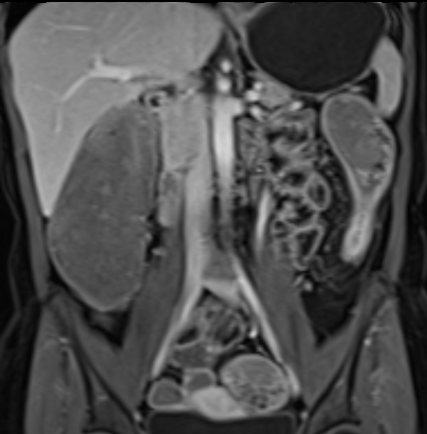

Bệnh nhân nữ 48 tuổi, đang điều trị bằng thuốc kháng TNF, được chỉ định nội soi đại tràng.

Phát hiện hẹp lòng ruột ở đại tràng sigma, không thể vượt qua được khi nội soi.

MR-enterography được thực hiện để đánh giá mức độ lan rộng của chỗ hẹp.

Cuộn qua các hình ảnh.

Ruột non bình thường, nhưng ghi nhận các đoạn hẹp ở đại tràng xuống và đại tràng ngang.

Cả hai đoạn hẹp đều có thành ruột dày đến 8 mm và ngấm thuốc rõ rệt theo kiểu niêm mạc ở đại tràng xuống và kiểu phân lớp ở đại tràng ngang.

Giãn ruột trước chỗ hẹp được ghi nhận ở cả hai đoạn.

Do các chỗ hẹp này không hiện diện khi nội soi đại tràng trước khi điều trị kháng TNF, nhiều khả năng chúng đã hình thành trong quá trình điều trị.

Do đó, quyết định phẫu thuật cắt đại tràng gần toàn bộ với miệng nối hồi-sigma đã được đưa ra.